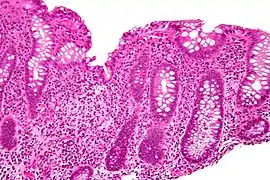

Cryptitis. H&E stain.

In histology, cryptitis refers to inflammation of an intestinal crypt.

Cryptitis is a non-specific histopathologic finding that is seen in several conditions, e.g. inflammatory bowel disease,[1] diverticular disease,[2] radiation colitis,[3] infectious colitis.